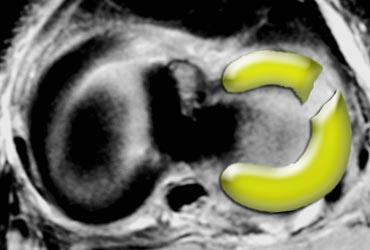

Dấu hiệu sụn chêm rỗng

Khi có rách xuyên tâm hoàn toàn, hai mảnh sụn chêm có thể bị tách rời hoàn toàn.

Điều này có thể dẫn đến hình ảnh khoang sụn chêm rỗng hay còn gọi là dấu hiệu sụn chêm rỗng (mũi tên).

TRÁI: Hình ảnh sụn chêm vắng mặt hoặc rỗng trên mặt phẳng đứng dọc. PHẢI: Hình ảnh mặt cắt ngang cho thấy rách xuyên tâm hoàn toàn dẫn đến khuyết hổng sụn chêm.

Nếu khảo sát một đường rách xuyên tâm hoàn toàn trực tiếp dọc theo chiều dài của đường rách, bạn sẽ thấy hình ảnh sụn chêm vắng mặt hoặc rỗng.

Các đường rách xuyên tâm hoàn toàn này mở ra và tạo ấn tượng rằng có một phần sụn chêm bị thiếu.

Tuy nhiên, bạn sẽ không tìm thấy mảnh sụn chêm bị di lệch.

Đây đơn thuần chỉ là sự tách rời của các phần sụn chêm.